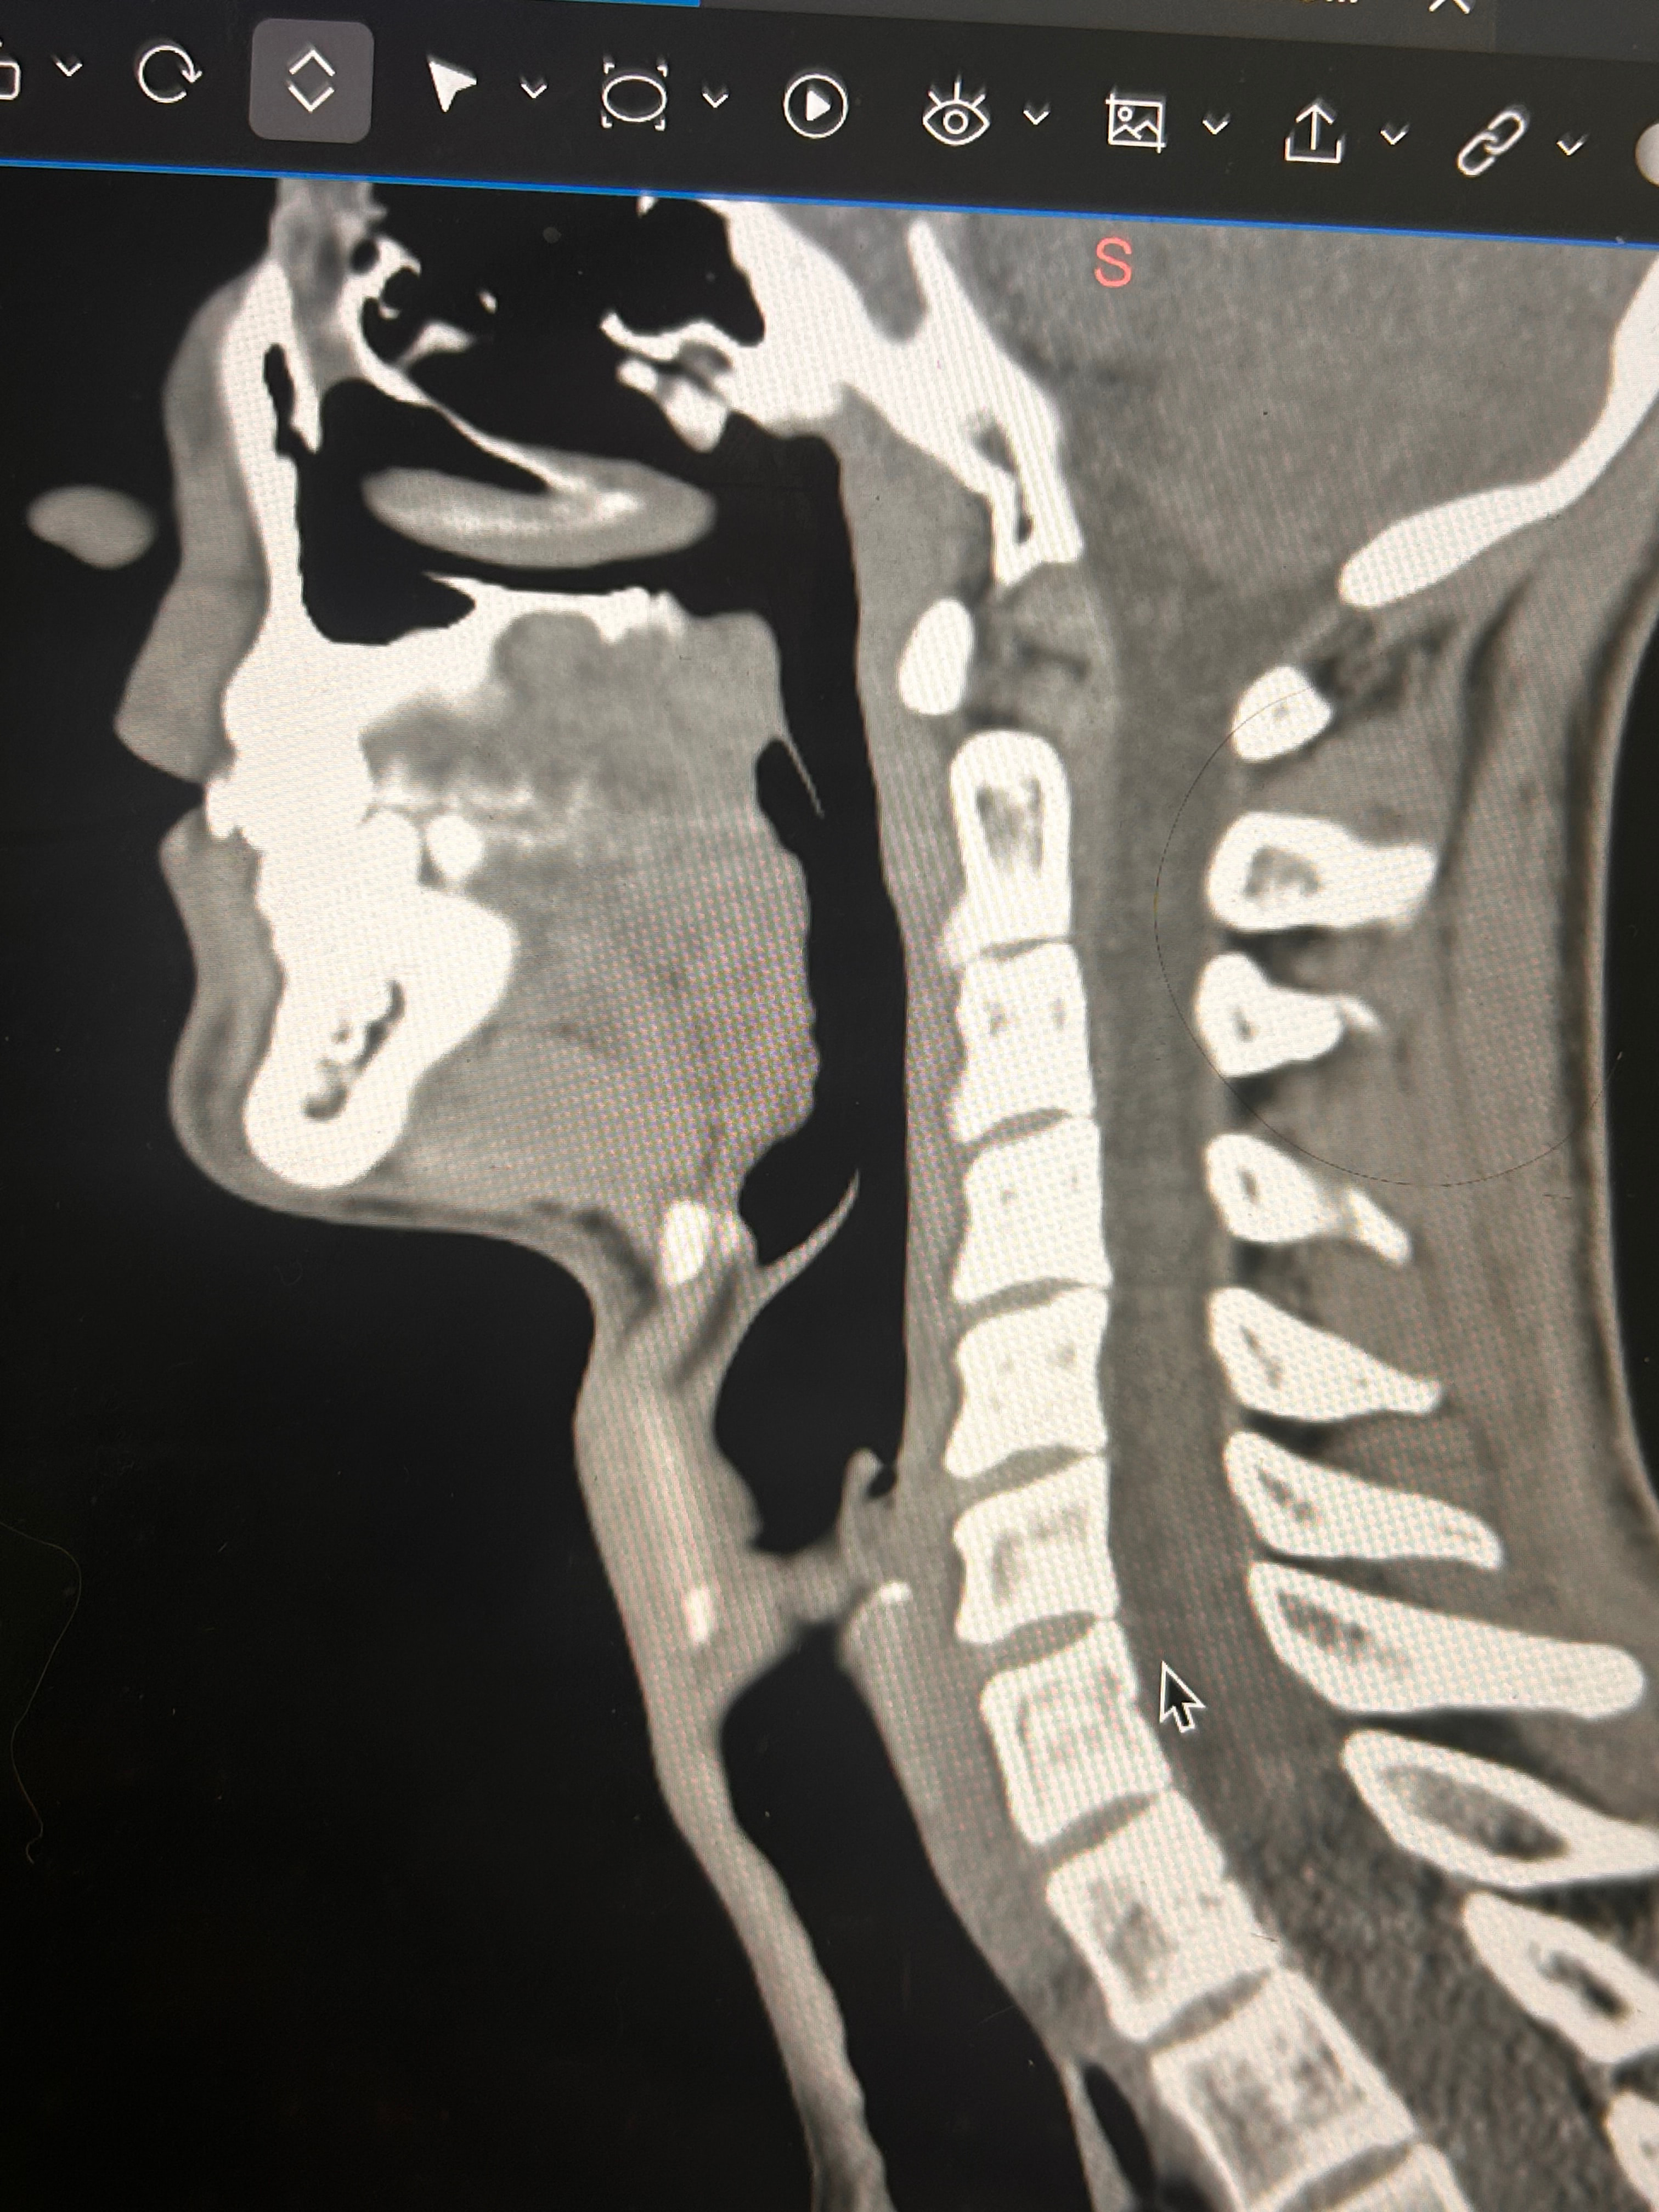

Here are some images of my 3-d ct, thanks for taking an interest it means a lot!

Oh and I almost forgot these were taken before I had my right styloidectomy

Things of note that I can see in your imaging - You’ve completely lost the natural lordotic curve in your cervical spine. That alone can bring the styloids & hyoid bone into closer proximity to nerves & vascular tissues in the neck though it has been speculated that the neck curve is lost when there’s IJV compression due to ES as the body’s way of trying to create more space for the IJV so it can drain the deoxygenated blood from the brain more efficiently. The lordotic curve can be restored w/ gentle exercises but it takes patience & is a slow process. The following link has helpful information about cervical curve restoration.

In this image of your left styloid, it appears from the angle of the picture that your left styloid is extremely close to the left transverse process of C1 (green circled area). If that’s truly the case, your left IJV is likely being squashed between the two & that means your vagus nerve is most likely being squashed at that point, too. Some of your symptoms could be vagal related. Also due to the angle of the image, it appears the greater horn of your hyoid could be very close to your spine which can cause internal/external carotid artery compression but can also cause symptoms that point to hyoid bone syndrome as you’ve suggested. Unfortunately, it doesn’t appear the CT scan was done w/ contrast as none of your veins or arteries appear in the images you posted & contrast is necessary to see those.

I’ll just add in as well that in your first image, the hyoid bone processes look pretty thick, more than you’d expect, so could well be part of your issues, but I do agree with @Isaiah_40_31 that your left styloid is very close to the C1 process, the right side looks a little longer than average… Also looking at the 1st & last images (I’m sorry, | can’t label them for you), there’s calcification below your hyoid which I’m presuming is the thyroid cartilage, it lookd pretty chunky compared to most people’s, so this could possibly be causing some issues too?

Yes these are from before my first surgery with Dr. Osborne and I had my right styloidectomy. I have also wondered about the cartilage. Last year I saw a couple of orthopedic doctors, one of whom suggested that I look into the cartilage because of how large it was and how it might be affecting my military neck and my ability to extend my neck.

Here are some of my 2-d scans, thanks. The top one is my right greater horn and the bottom is the left

Thank you for the additional images. After reading @Jules observations, I went back over the first 4 images you sent & realized I’d miss some significant things. I’ve annotated more images for you below: